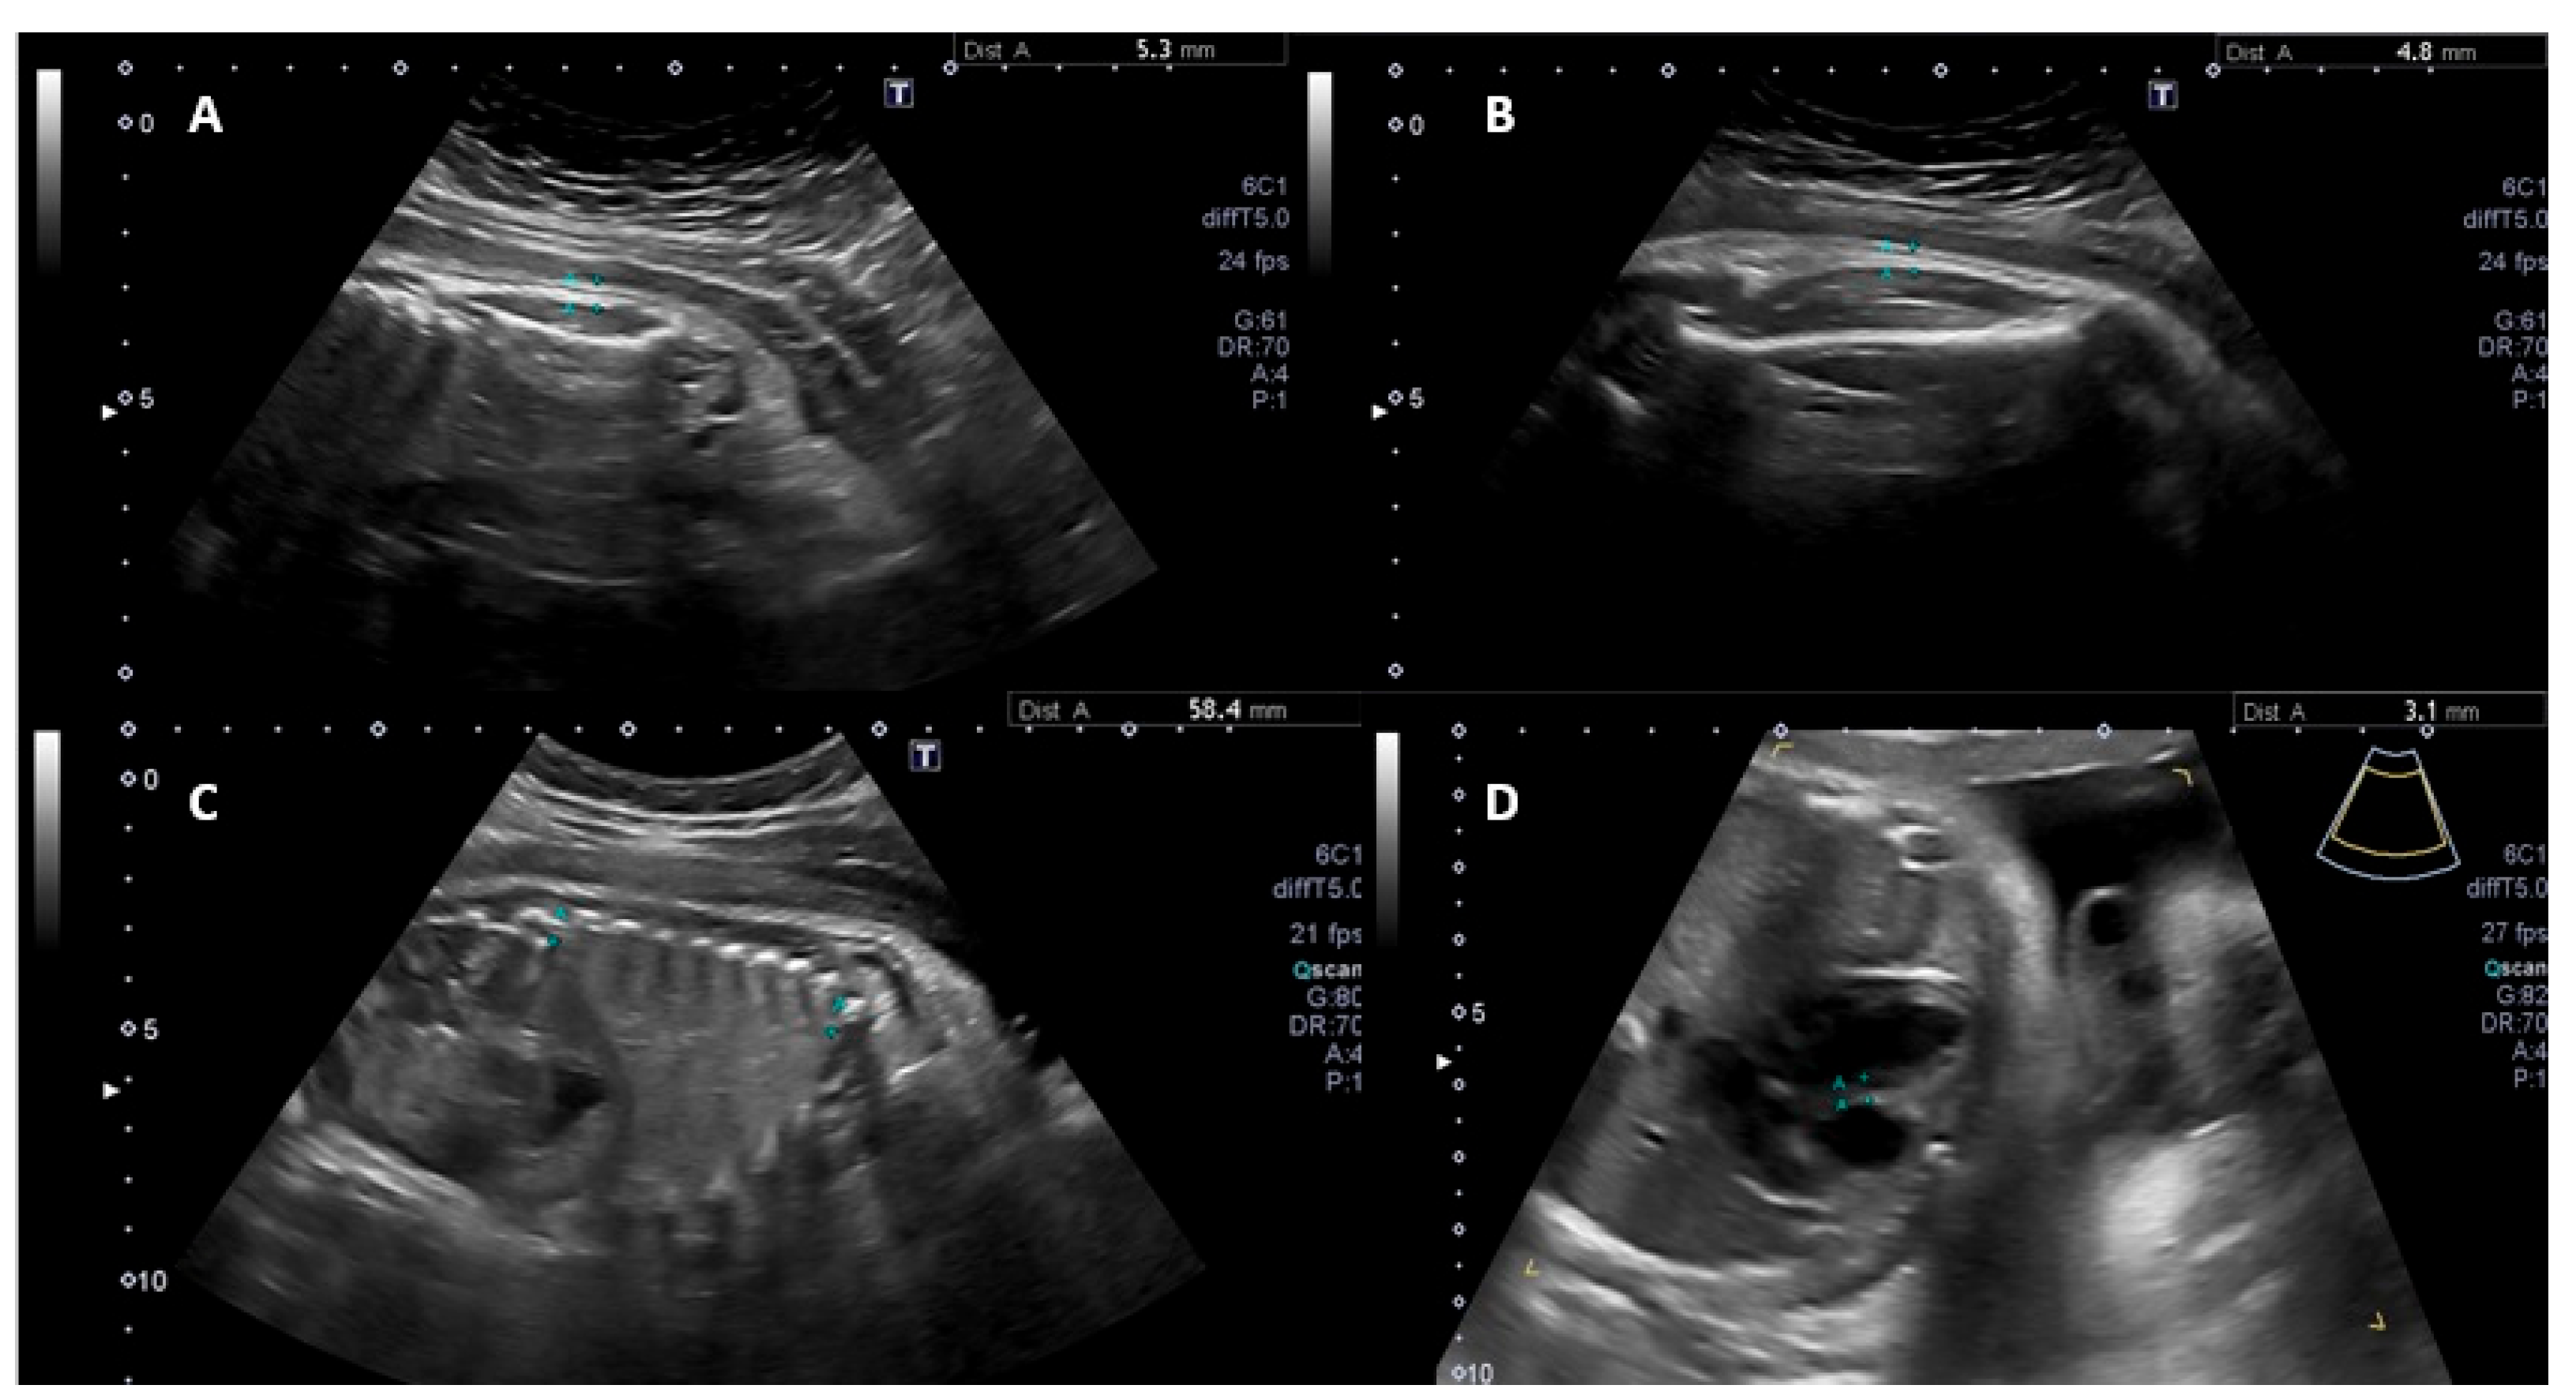

2. Methods